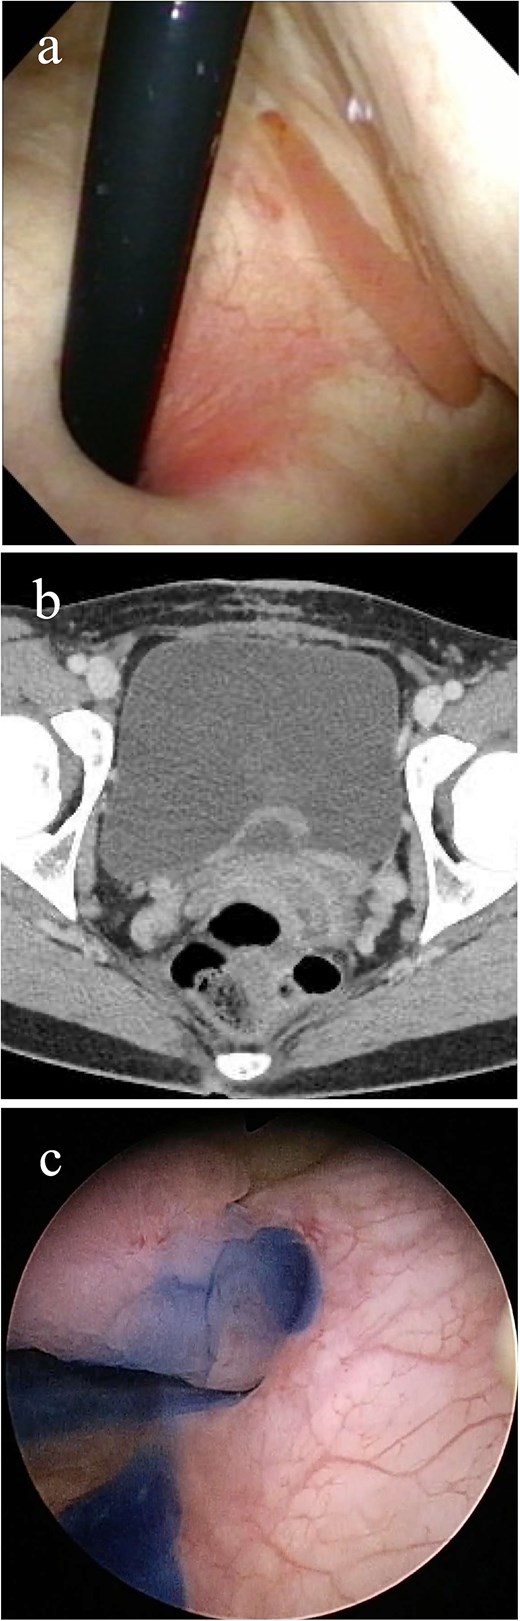

Imaging study findings. (a) Cystoscopy finding. Cystoscopy revealed that a tumor protruded from the left ureteral orifice into the bladder lumen, showing serpentine locomotion with respiratory movements. (b) Contrast enhanced computed tomography finding. Soft tissue shadow was detected around the left ureteral orifice, revealing a long thin tumor. (c) Indigo carmine was excreted through the left orifice that is occupied by the tumor.

The patient underwent detailed endoscopy in the operating room (Video 1). The indigo carmine test revealed patency in the ureteral orifice occupied by the tumor (Fig. 1c). A ureteroscope was inserted along the tumor into the left ureter. The lower ureter was occupied nearly completely by the tumor, but the ureteroscope could pass through the small gap between the tumor and the ureteral wall. As the scope reached the mid-ureter, the root of the tumor eventually became thinner, and a single narrow base of the tumor was identified. FEP was diagnosed based on the characteristic surface findings and root shape of the tumor. Because this polyp could be safely removed ureteroscopically, ureteroscopic resection was performed using a Holmium: YAG Laser (0.3 J, 10 Hz). Electrocautery was applied to the base of the polyp, and the coagulation area was kept as small as possible. Finally, the polyp was resected and extracted entirely from the ureter and into the bladder lumen using forceps. A double-J stent was inserted, and the ureteroscopic procedure was completed. The stent was removed a month after the surgery. Her gross hematuria stopped, and she reported no complications. Histopathological examination revealed a 9.5 cm tumor and a polyp with edematous stroma, which was confirmed to be ureteral FEP (Fig. 2a and b).

Similar to this case, there have been some reports of FEP protruding into the bladder [4, 7, 8]. In such cases, staining urine with intravenous indigo carmine is useful for checking ureter patency and determining whether ureteroscopic management is feasible [11]. If the ureteroscope is successfully inserted and the root of the tumor is observable, thin, and single, ureteroscopic resection is considered. When the polyps are significantly large or multiple, they occupy the lumen of the ureter and are difficult to distinguish from the ureteral wall, making visualization poor [1, 3, 5]. Ureteral stricture is the most common complication of ureteroscopy [10]. Ureteral strictures occurred in 1.8% of patients who underwent treatment of FEP ureteroscopically [1]. Therefore, if the tumor root is significantly large and extends almost halfway through the ureteral wall, treatment options other than ureteroscopy should be considered to avoid postoperative ureteral strictures.